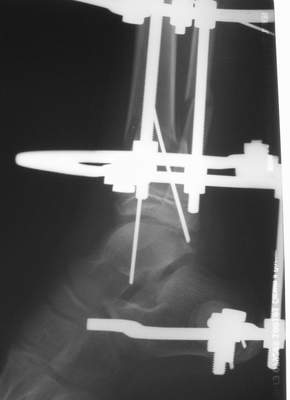

Перелом костей н\3 правой голени со смещением. Перелом большеберцовой кости можно охарактеризовать как компрессионно-оскольчатый.

Скелетное вытяжение за пяточную кость.

Операции: 1 Клиновидная резекция на вершине деформации м\берцовой кости.

2 Тугоподвижный ложный сустав н\3 б\берцовой кости. Рубцы выполняющие пространство между отломками, канал проксимального отломка иссечены.

Одномоментное устранение деформации, остеосинтез Г-образной пластиной.

Пластика по Хахутову.

Вытяжение

|

Фиксация